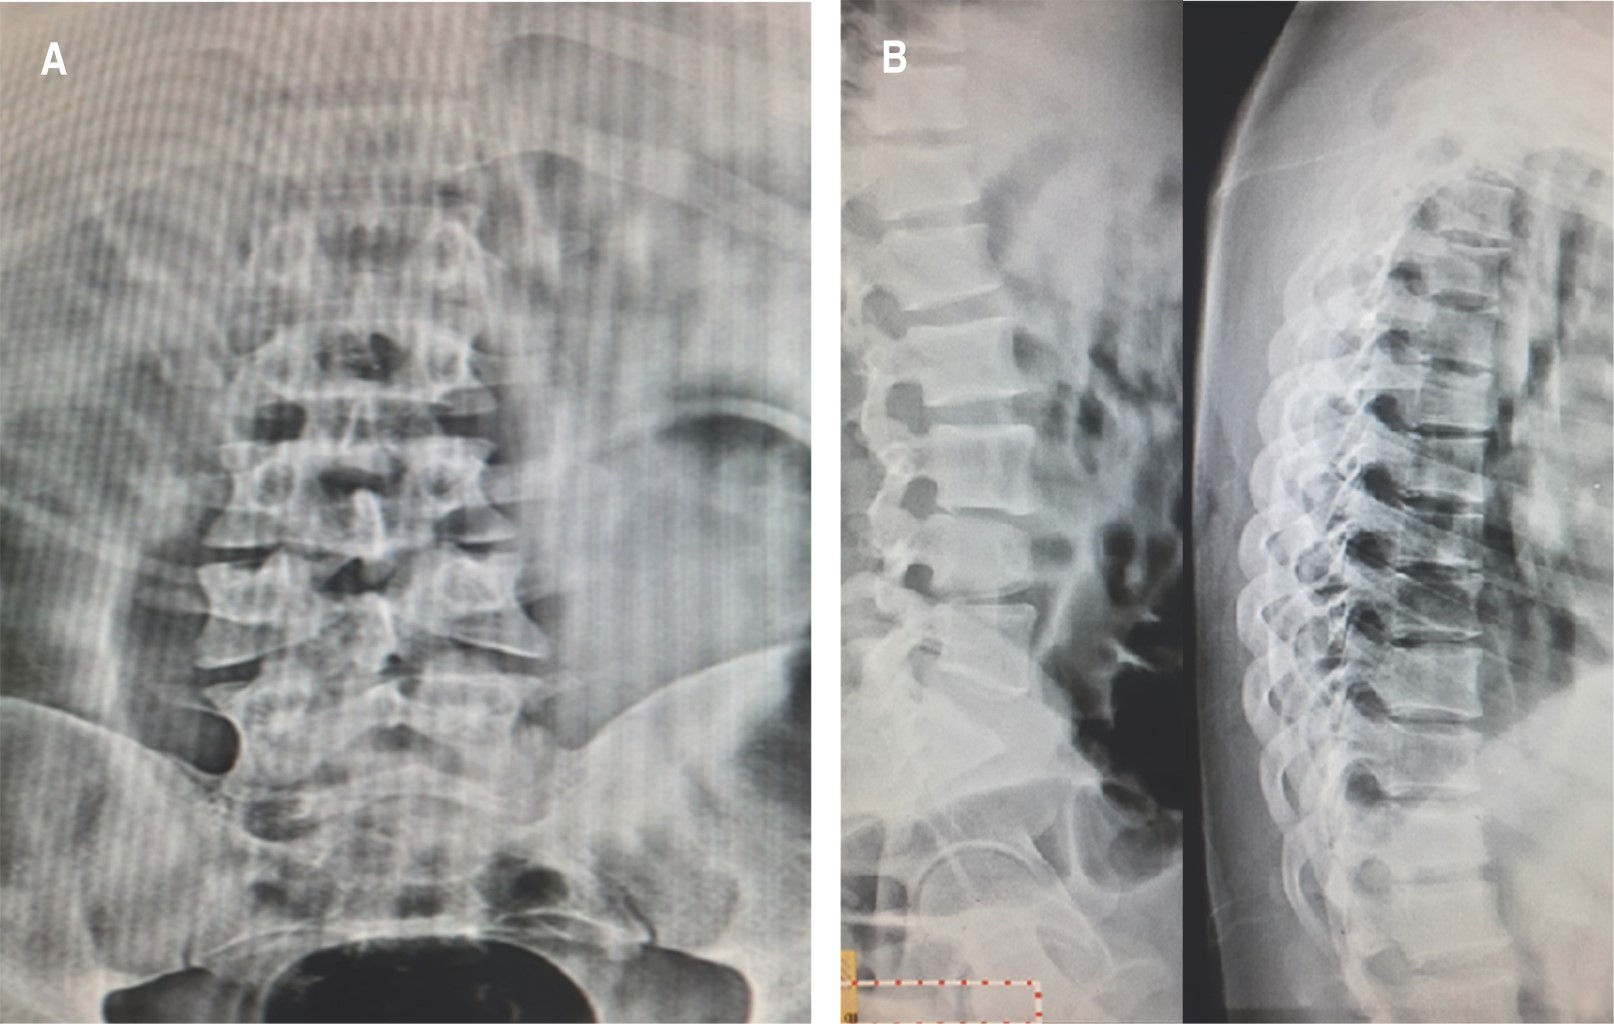

El examen radiográfico demostró rectificación de la columna cervical, además en radiografía lateral de columna lumbar se observó disminución de la plataforma superior del cuerpo vertebral de L4, con afectación de columna anterior y media de Francis Dennis, sin retropulsión a conducto medular, también en radiografía anteroposterior (AP) de columna lumbar se advirtió una incongruencia a nivel de L4 con ausencia de fusión de cuerpos vertebrales con diástasis de ocho milímetros (Figura 2).